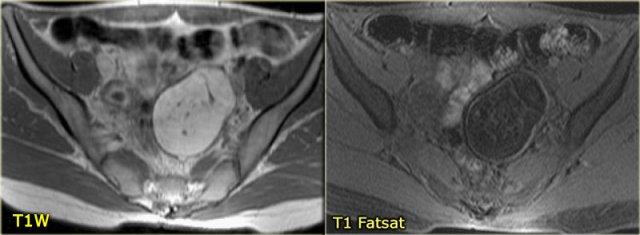

Trên chuỗi xung T1W không có kỹ thuật xóa mỡ, nang phức tạp tăng tín hiệu, gợi ý thành phần mỡ hoặc máu.

Trên chuỗi xung T1W có kỹ thuật xóa mỡ, tổn thương vẫn tăng tín hiệu, loại trừ tổn thương chứa mỡ.

Sau khi tiêm Gd, không có ngấm thuốc, xác nhận đây là nang buồng trứng xuất huyết.

Lạc nội mạc tử cung dạng nang (endometrioma) cần được đưa vào chẩn đoán phân biệt.

Lưu ý rằng hình ảnh trừ (subtraction) là tốt nhất để chứng minh sự vắng mặt của ngấm thuốc trong tổn thương tăng tín hiệu trên chuỗi xung T1W trước tiêm thuốc tương phản từ.

Trên hình ảnh chuỗi xung T1W mặt cắt ngang, cả hai tổn thương đều tăng tín hiệu, gợi ý mỡ, máu hoặc dịch giàu protein.

Kỹ thuật xóa mỡ không làm giảm tín hiệu trong các tổn thương này.

Trong một hình ảnh có kỹ thuật xóa mỡ tổng thể tương đối tốt, điều này loại trừ u quái chứa mỡ và xác nhận gợi ý về dịch xuất huyết.

Trên hình ảnh chuỗi xung T2W mặt cắt ngang, cả hai tổn thương đều cho thấy hình ảnh ‘shading’ điển hình.

Sự sụt giảm dần dần tín hiệu T2 được cho là do sự kết hợp của độ nhớt tăng dần và nồng độ protein cùng sắt tăng dần về phía phần thấp của tổn thương.

Không có ngấm thuốc trên hình ảnh trừ (sau tiêm Gd trừ trước tiêm Gd).

Một lần nữa, kỹ thuật trừ rất hữu ích trong các trường hợp như thế này: sự tăng tín hiệu do Gd gây ra trên nền hình ảnh trước tiêm thuốc vốn đã rất sáng sẽ rất khó nhận biết nếu không có kỹ thuật này.